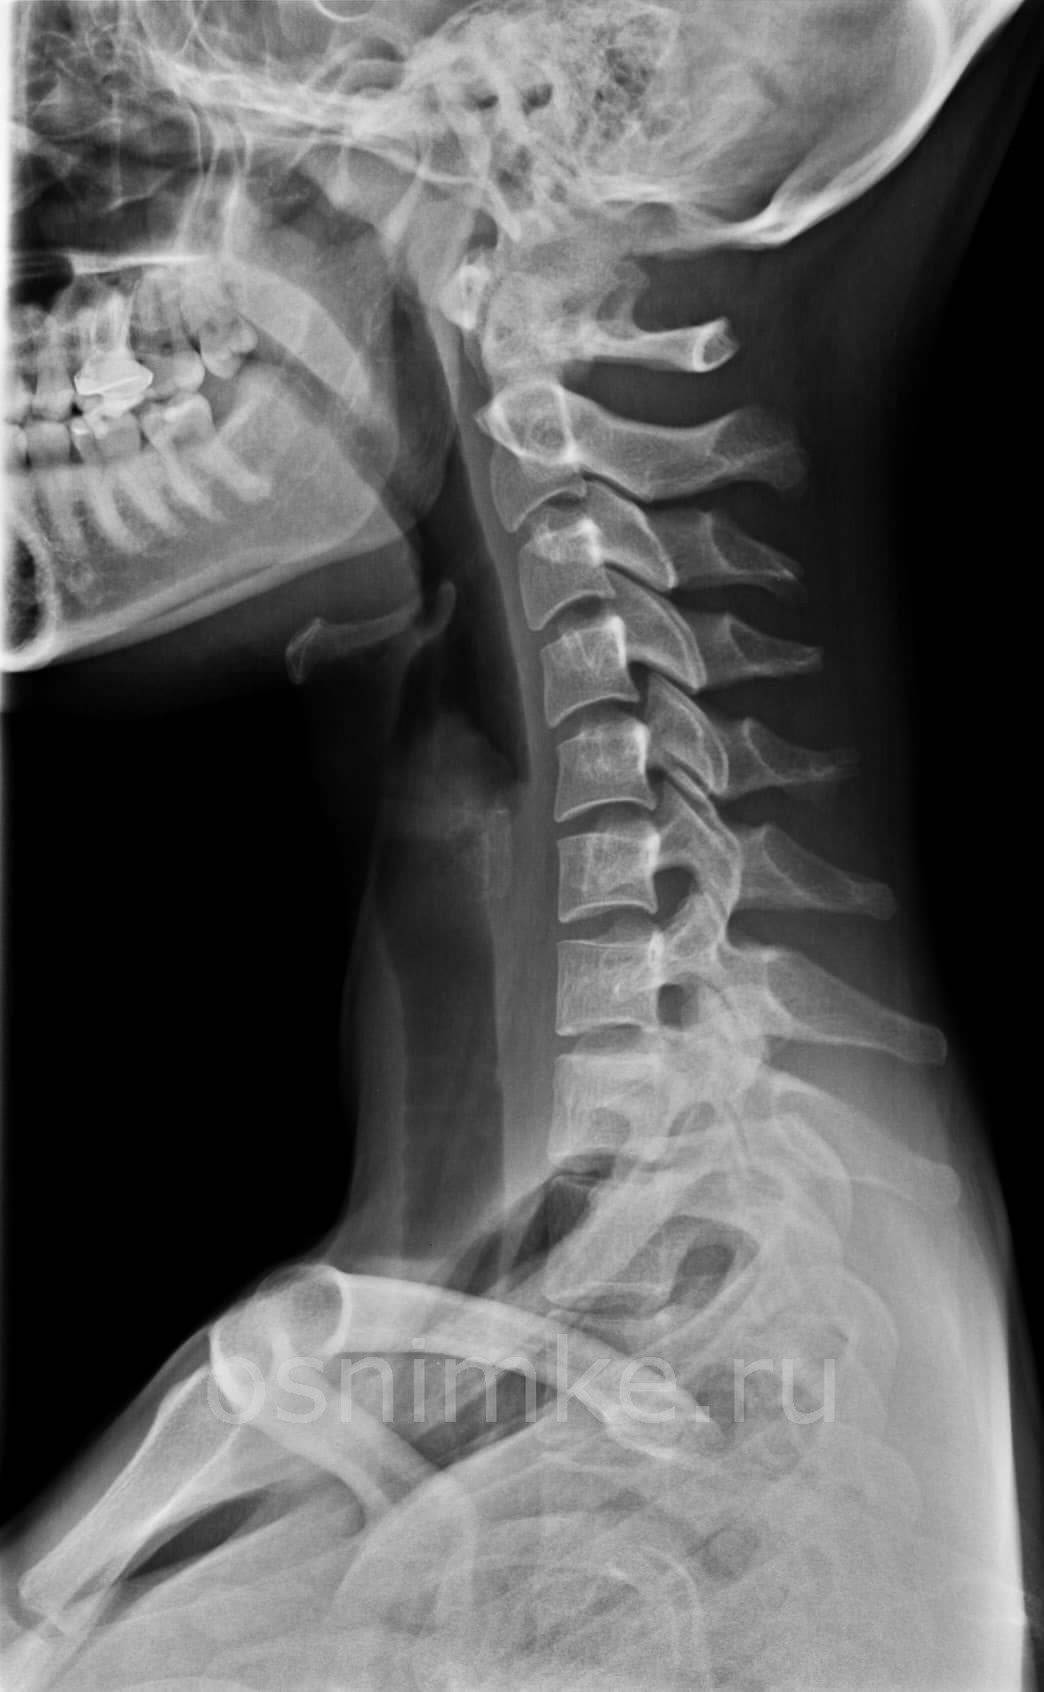

Рентген шейного отдела позвоночника: показания и особенности проведения

Шейный отдел позвоночного столба является сложной для визуализации структурой, поскольку здесь находятся сосуды, мышцы, связки, кости, сухожилия, межпозвоночные диски. Чрезвычайно важным является отдел и потому, что в толще позвонков залегает спинной мозг, передающий импульсы в различные отделы человеческого тела. Здесь же расположены и крупные кровеносные сосуды, питающие головной мозг. Даже незначительная травма способна отразиться на работе органов кровоснабжения и центральной нервной системе.

Рентгенография шейного отдела позвоночника показана при таких заболеваниях:

- остеохондроз;

- травмы у детей, полученные в результате родовой деятельности;

- кифоз;

- спондилез;

- врождённые аномалии в шейном отделе;

- шейный лордоз;

- артрит;

- деформации межпозвоночных дисков;

- шейный радикулит;

- онемение конечностей;

- хруст при повороте головы;

- опухоли или их метастазы;

- головная боль невыясненного происхождения.

Чаще всего в результате рентгенологического исследования обнаруживается остеохондроз и межпозвоночные грыжи.